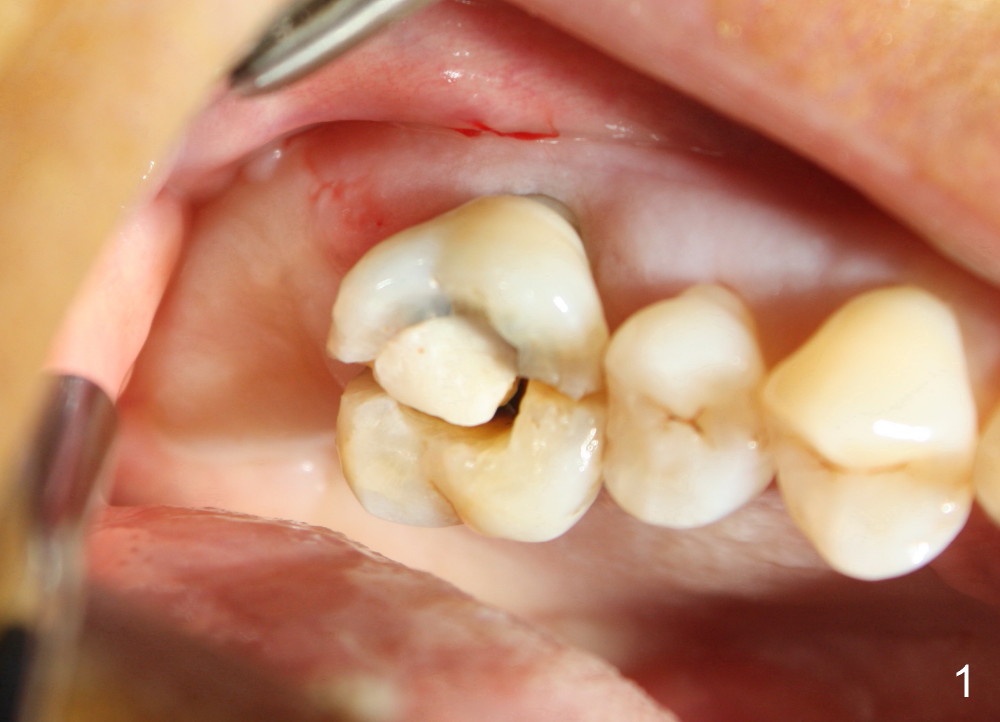

The upper right 1st molar fractures, the lingual portion mobile (Fig.1). There are deep pockets mesiolingually and distolingually. Fig.2 is preop PA, showing mesial bone resorption (*). The 84-year-old lady agrees extraction and immediate implant. Extraction is difficult due to not only root fracture but also hemorrhage. Following debridement of granulation tissue, the 3 sockets are packed with gauze for hemostasis. Even so, there is oozing from the bone. The septum can not be seen clearly. Its position is determined by an explorer. Osteotomes have to be used for osteotomy in the septum, followed by taps. The first intraop PA shows that 5x20 mm tap penetrates the sinus floor (Fig.3 ^). The osteotomy is further enlarged until 7x17 mm tap with stability (Fig.4). So far there has been no sign of sinus membrane perforation. Mixture of freeze dry mineralized bone and Osteogen is placed in the socket and pushed to the buccal and lingual walls as well as into sinus using a 4 mm flat end osteotome. A 7x17 mm implant is initially difficult to be inserted possibly due to blockage by bone graft. The osteotomy have to be recreated by a series of osteotomes and taps before placement of the 7x17 mm implant. It appears that the apical threads have been engaged into the sinus floor for primary stability (Fig.5). The insertion torque is 40 Ncm. According to our experience (1,2), this is not enough; finally the torque is increased to 60 Ncm by turning the implant more apically. The large implant obliterates the socket mesiodistally; the buccal and lingual gaps are filled with bone graft, followed by a collagen membrane (Fig.6 *) and suture. In order to protect the membrane, a short abutment is placed (A) and perio dressing (Fig.7*) is placed without occlusal interference. The abutment is removed 1 month postop, as the perio dressing has been dislodged. The patient returns for restoration 8 month postop. Bone regeneration occurs apparently in the coronal aspect of the implant (Fig.8), especially mesially (*, as compared to Fig.5). The gingiva-level implant is slightly subgingival mesially (Fig.9 M), probably due to high placement (compare to Fig.6). There is no bone resorption 6 months post crown (Fig.10 C) cementation.